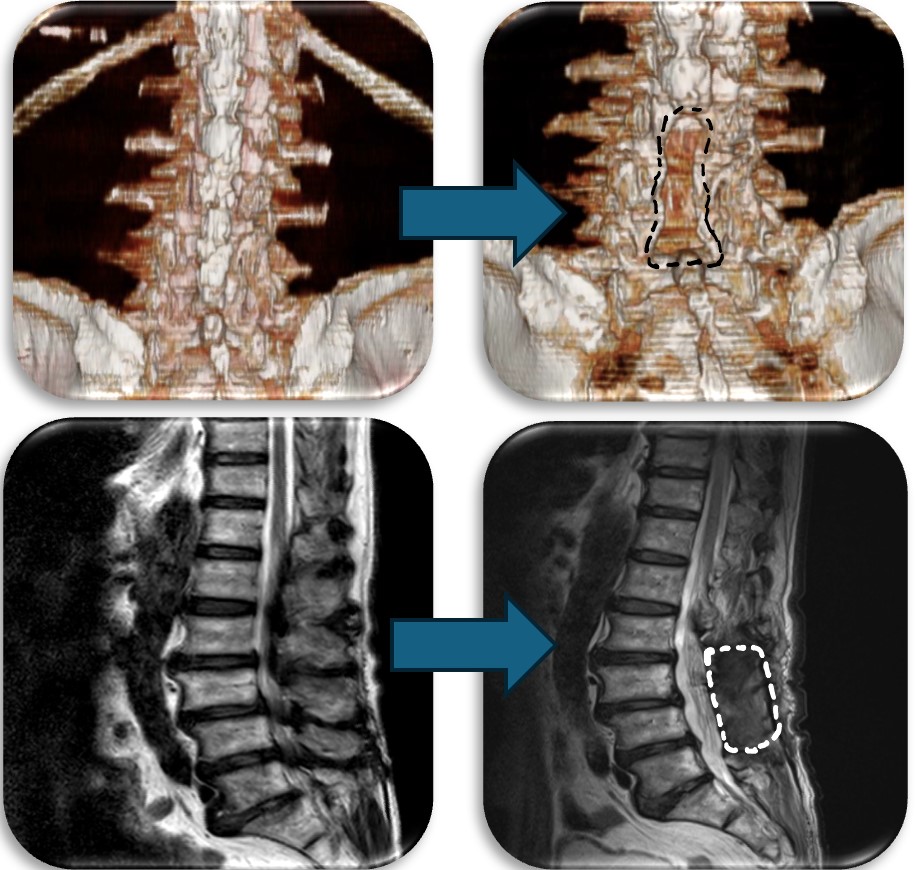

(代表例②)

腰部の脊柱管狭窄症に対して、腰の後ろから手術する椎弓切除術を行なった症例です。脊柱管と呼ばれる脊髄が通るトンネルの屋根部分にあたる椎弓を切除(点線部分)することによって狭かった脊柱管を広げます。